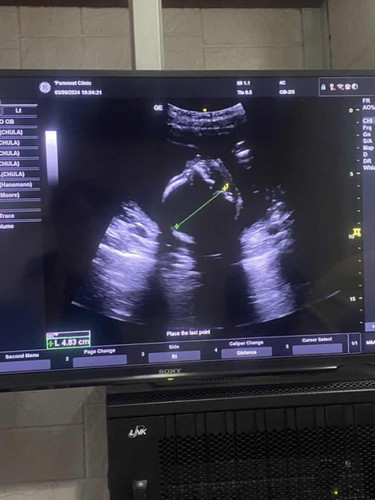

แม่ๆ 20 W น้องหนักกี่กรัมกันค่ะ เรา 20+3 นน. 500 กรัม แม่กินแซ่บมากค่า ได้ลูกสาว 😂😂😂 #ท้องแรก

ไม่เล็กนะแม่ ถ้าหมอไม่บอกว่าตัวเล็กน้องก็ไม่เล็กค่ะ บ้านนี้ซาวล่าสุด19+5วีค 354กรัม ตอนนี้21+6วีคแล้วค่ะ

บ้านนี้ 20w+4น้ำหนักน้อง 432 กรัมค่ะ หมอบอกว่าน้ำหนักตามเกณฑ์ น้องจ้ำม่ำอยู่ค่ะ #แม่นี่อยากเจอลูกแล้ว

บ้านนี้21สัปดาห์1วัน 512กรัมคะ หมอบอกโตกว่าเกณฑ์นิดหน่อย😂

บ้านนี้แม่ท้อง22วีค น้องมีน้ำหนัก478กรัมค่ะ

เราซาวตอน19+ หนัก293เองคะ

ของเรา 22 W น้องหนัก 600 🤣

21 วีค 460 g ค่ะ

21w 382g จ้าาา